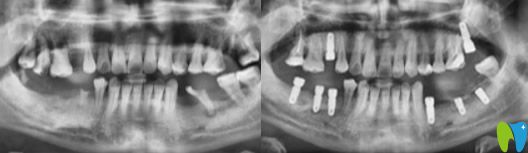

術(shù)前問(wèn)題:下頜磨牙掉的只剩一顆,上頜情況也不容樂(lè)觀,并有多顆牙松動(dòng)。

解決方案:通過(guò)數(shù)字化技術(shù),精準(zhǔn)地在梁女士缺牙位置植入種植體,一些無(wú)法保留的牙齒采取了即拔即種治療,解決了她多年的缺牙問(wèn)題。